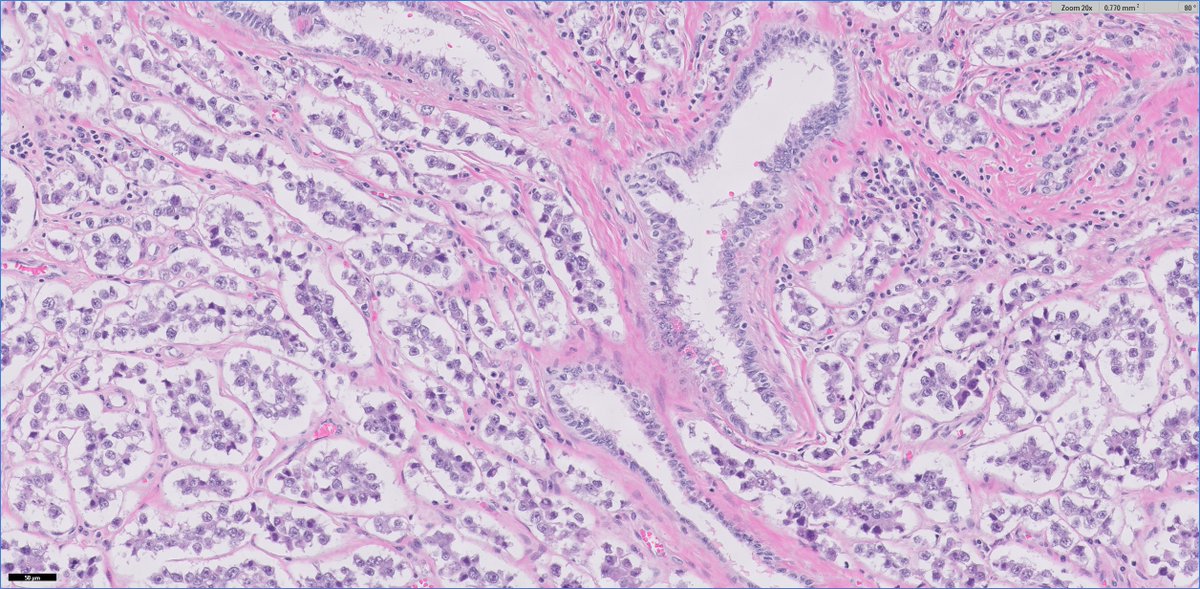

#GUpath🧩 time!

30ish M (no priors) presents with testicular mass and undergoes radical orchiectomy

🔬🤔❓